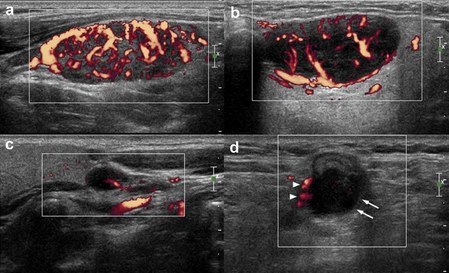

Çocukluk çağlarında boyunda en fazla saptanan şikayetler şişliklerdir. Sıklıkla bu şişlikler enfeksiyona bağlı büyüyen lenf bezleri ile oluşur. Büyümüş lenf nodlarının enefeksiyona bağlı gelişmiş iyi huylu lenf nodları mı ya da hematolojik-onkolojik hastalıklara bağlı gelişmiş kötü huylu lenf nodları mı olduğunu büyük oranla ultrason ile saptayabiliriz. Genellikle hareketli ve ağrılı lenf nodları enfeksiyonu düşündürmekle birlikte ayırıcı tanının tam olarak yapılabilmesi ve boyut ölçülmesi için ultrason yapılmalıdır.